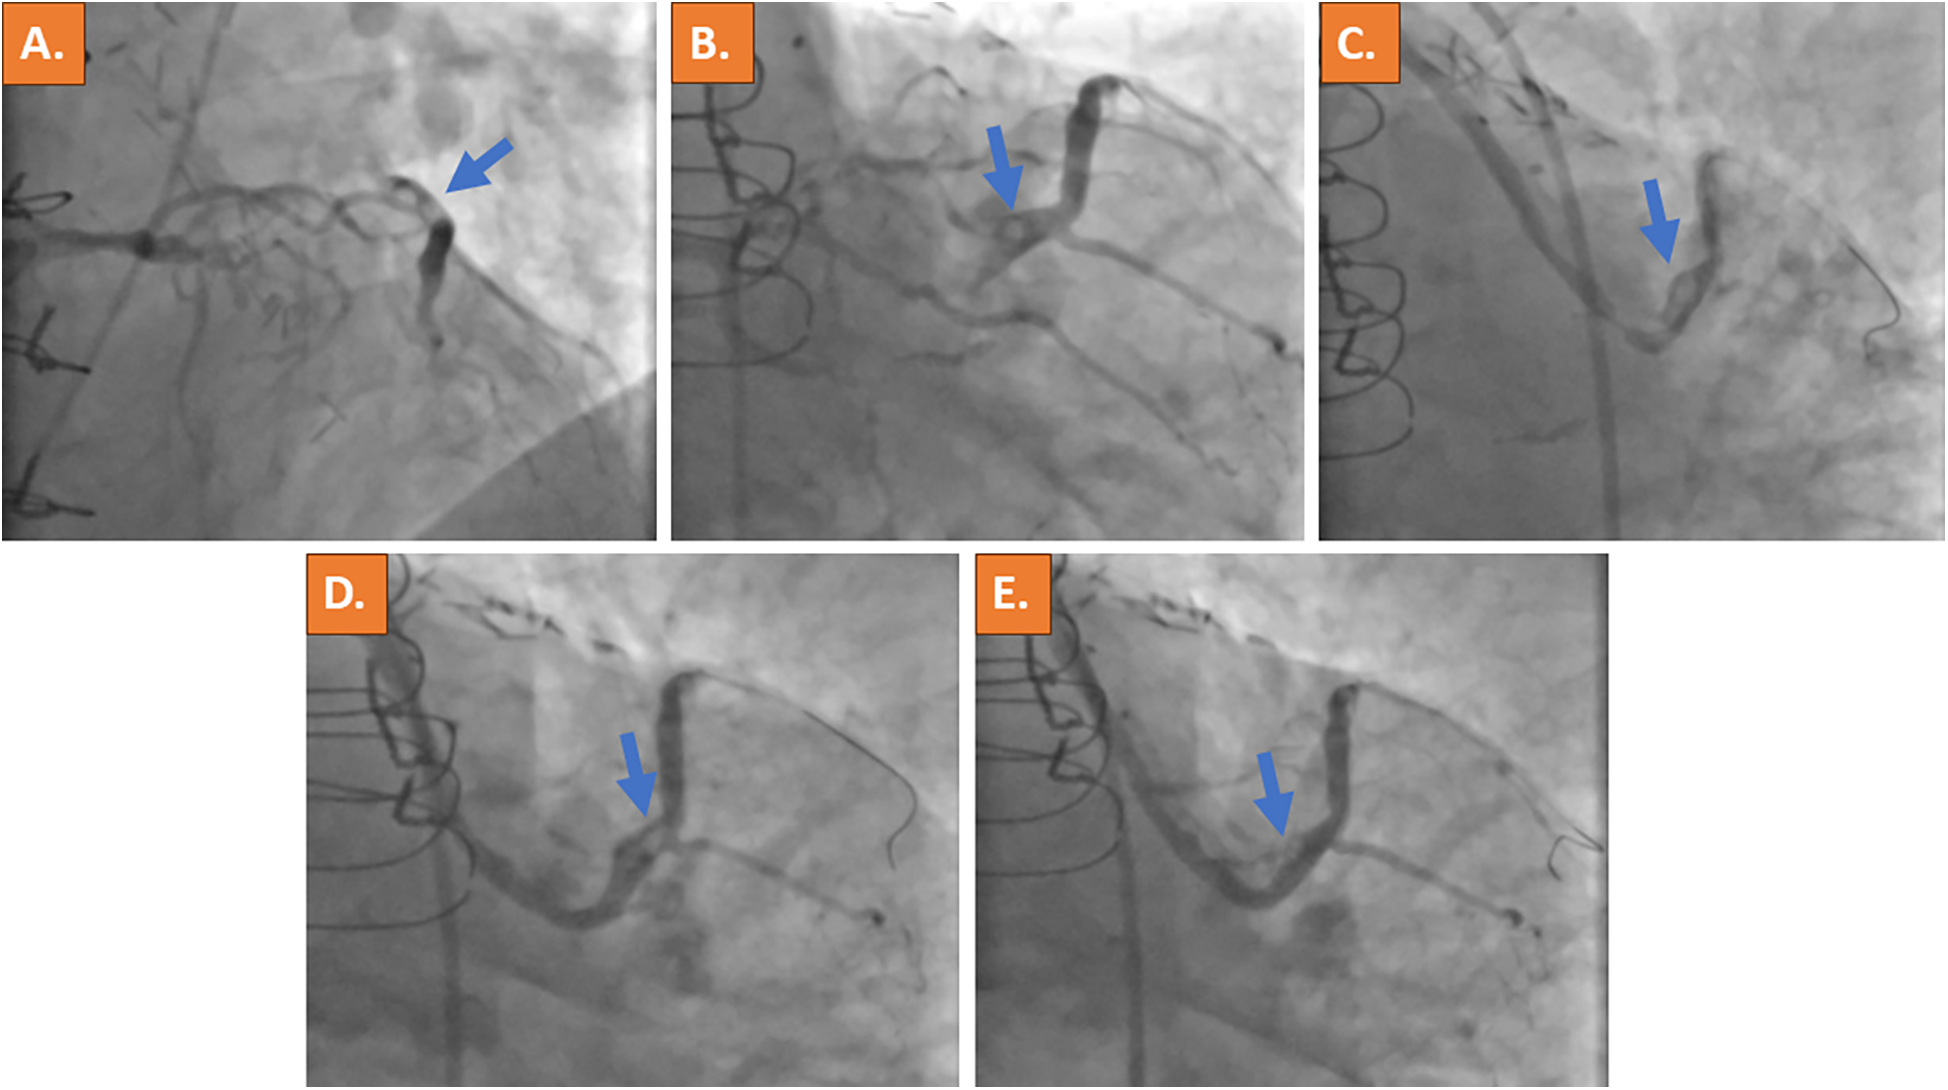

Cardiac catheterization was performed urgently on the same day using the right common femoral artery and showed occlusion of all three native coronaries (syntax score of 62). Calcification was non-severe in all three coronary arteries and no collaterals were noted. Selective angiography of the left coronary artery revealed retrograde filling of the saphenous vein graft (SVG) through the first diagonal branch. The SVG showed a very tight stenosis at the distal anastomosis with thrombus being responsible for TIMI flow grade 2 (Figures 2A,B, Supplementary Videos 1A,B,E,F). The left internal mammary artery graft to the left anterior descending (LAD) coronary artery was found patent (Supplementary Video 1C), whereas a good long-term result after PCI and stent placement 7 years ago was observed in the vein graft to the RCA (Supplementary Video 1D). Using a 6 French (6F) Amplatz left curve (AL) guiding catheter and a SION blue guidewire (ASAHI) for lesion crossing and thrombus, aspiration was subsequently attempted using a 6F catheter (Eliminate™, Terumo); however, it was not possible to advance the thrombectomy catheter through the high-grade stenosis. An intravascular ultrasound (IVUS) catheter could also not be advanced through the lesion. In addition, since the lesion and the thrombus were located at the distal part of the bypass graft, the placement of an embolic filter protection device was not deemed technically feasible. Activated clotted time (ACT) was controlled, being at 325 s at this time point. After lesion predilatation using a 2.0×15 mm semi-compliant balloon, two DESs (3.5 mm × 16 mm and 4.0 mm × 12 mm) were deployed with short overlap. However, the remaining thrombus was noticed distally to the implanted stents (Figure 2D, Supplementary Video 1G). The implantation of another DES was deferred in the absence of residual vascular plaque and due to the risk of distal embolization with bypass graft occlusion. Instead, an intra-arterial injection of 10 mg Actilyse (recombinant tissue plasminogen activator, rt-PA; Boehringer Ingelheim, Ingelheim, Germany) was performed through the guideliner directly to the thrombus, which resulted in substantial thrombus reduction within 15 min (Figure 2E, Supplementary Video 1H).

Figure 2

Acute invasive coronary angiography with selective contrast material injection into the left coronary artery ostium revealed retrograde filling of the vein bypass graft to the large first diagonal branch with suspected thrombus formation at the distal site of the bypass anastomosis (blue arrows in A,B). A high-grade stenosis of the vein graft was present (C). After PCI, a remaining thrombus was noticed distally to the implanted DESs (D). Because thrombus material remained, intra-arterial application of thrombolysis (rt-PA) was performed and significantly reduced the clot burden (E). The thrombotic material is indicated by the blue arrow.